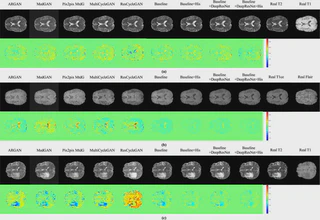

Magnetic Resonance Imaging (MRI) and Computed Tomography (CT) are commonly used tools for medical diagnostic assessment. Considering the ionizing radiation of CT imaging, estimating CT images from radiation-free MRI would be beneficial for medical diagnosis. Although state-of-art generative adversarial networks or end-to-end architecture models can generate realistic natural images, it is challenging to generate medical CT images with high signal-to-noise ratios and are paired with MRI. We propose a histogram-driven generative adversarial network (HisGAN) to address this issue, estimate CT images paired with MR, and develop a histogram-based dynamic scaling factor to facilitate learning different image styles. By employing an adversarial learning strategy to train the end-toend generator, the generator better simulate the nonlinear mapping from source to target. For the generator, the proposed method applies multiple learnable parameters to adjust the overall weights of the dilated convolution layers to ensure sufficient expansive receptive fields for improved performance. Additionally, the method utilizes deep residual networks to train randomly smoothed generated images and employs adversarial loss to enhance the generation of the discriminator, achieving a balance between the generator and the discriminator. Our approach can synthesize image details at the pixel level in the target domain and has been evaluated using two datasets for MR to CT, T1 to T2, and Flair to T1ce modality synthesis tasks. The proposed method outperforms existing generative adversarial models applied to medical image synthesis.